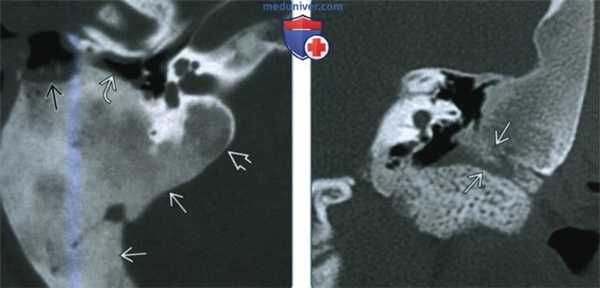

(Слева) При аксиальной КТ в костном окне определяется фиброзная дисплазия (ФД) склеротического типа, с поражением сосцевидного отростка и внутреннего уха и обрастанием задних отделов среднего уха. Экспансивный характер ФД приводит к стенозу наружного слухового канала (НСК). Обратите внимание на область ранее выполненной биопсии спереди и снаружи.

(Справа) При корональной КТ в костном окне определяется склеротическая ФД, приводящая к окклюзии НСК. Можно предположить наличие клинически значимой кондуктивной тугоухости. При отоскопии определяются изменения, схожие с врожденной мальформацией ИСК.